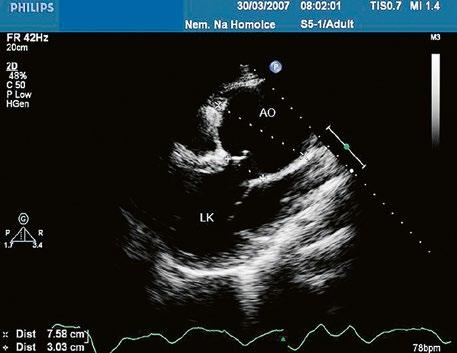

Obr. 45.24 TTE, parasternální dlouhá osa, těsně pod aortální chlopní (AO) je patrná diskontinuita v oblasti membranózního septa (šipka) s levopravým zkratem mezi levou komorou a pravou komorou LK – levá komora, LS – levá síň, PK – pravá komora

Poslechově má malý VSD typický hlučný systolický šelest vlevo parasternálně ve 3.–4. mezižebří. Velký nerestriktivní VSD s plicní hypertenzí nemívá tento typický šelest, ale pouze akcentaci 2. ozvy nad plicnicí. Echokardiografie je hlavní diagnostickou metodou (Obr. 45.24−45.35, Video 45.22−45.36).